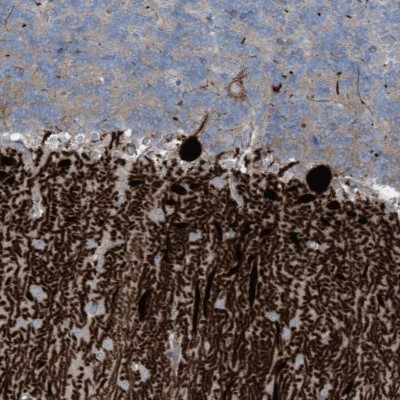

- Main image

- Experimental details

- Immunohistochemistry-Paraffin: ARHGEF33 Antibody [NBP1-91008] - Staining of human cerebellum shows strong cytoplasmic positivity in purkinje cells.